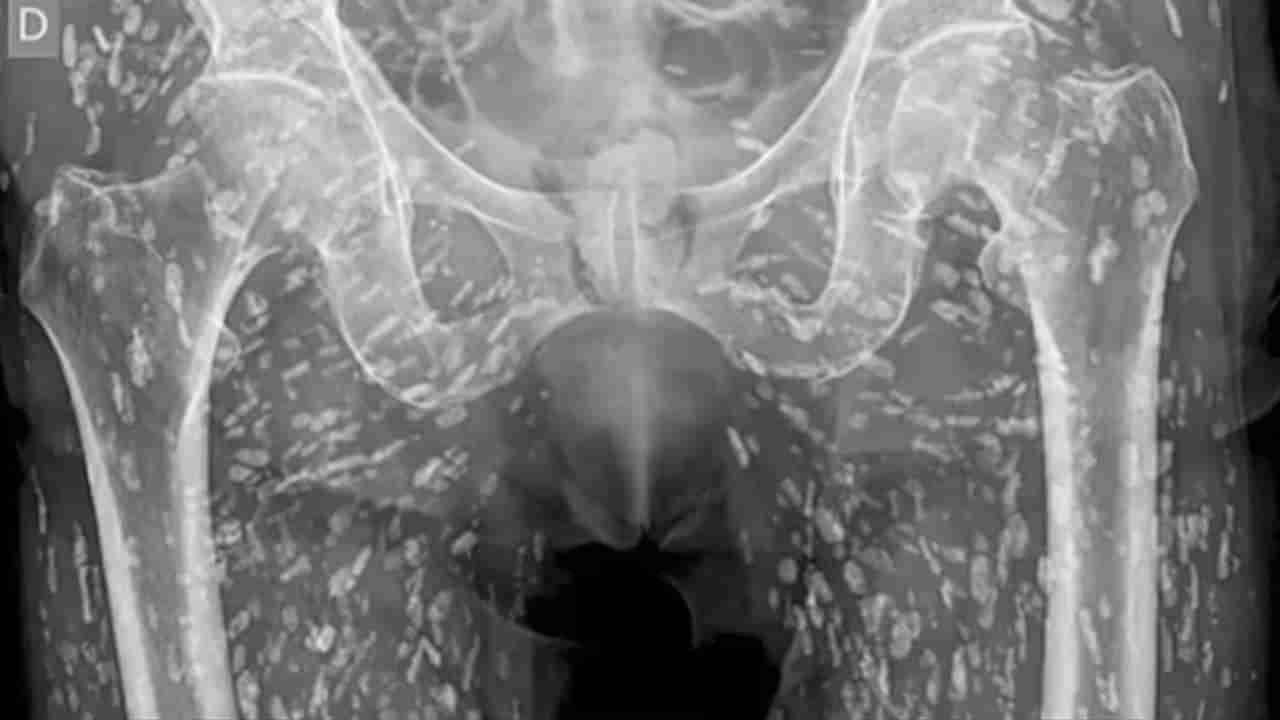

సాధారణంగా డాక్టర్లు ప్రతీ రోజూ చిత్రవిచిత్రమైన కేసులు చూస్తుంటారు. అలాంటి ఓ కేసు స్టడీ ఇది. డాక్టర్ శామ్ ఘలి దీనిని ఇంటర్నెట్లో షేర్ చేశారు. ఓ మెడికల్ కేస్ స్టడీలో భాగంగా పరాన్నజీవులు నిండిన ఒక ఎక్స్రే సోషల్ మీడియాలో తెగ వైరల్ అవుతోంది. సరిగ్గా ఉడకని పంది మాంసం తిని.. ఓ వ్యక్తి శరీరమంతటా కాల్సిఫైడ్ పరాన్నజీవులు ఫామ్ అయ్యాయి. ఇలా పరాన్నజీవులు నిండిన ఈ వ్యాధిని ‘సిస్టిసెర్కోసిస్’ వ్యాధి అని పిలుస్తారట. లార్వా తిత్తులు సోకిన పచ్చి లేదా ఉడకని పంది మాంసం తినడం ద్వారా పరాన్నజీవులు మనుషులకు సోకుతాయన్నారు. ఈ టేప్వార్మ్లు మానవ శరీరంలో కొద్ది వారాల్లో పరిపక్వత చెంది.. గుడ్లు పెట్టి.. మరిన్ని టేప్వార్మ్లను ఫామ్ చేస్తాయి.

టేప్వార్మ్ లార్వాలు మానవ శరీరంలోని మృదు కణజాలాలలోకి చేరి వృద్ది చెందుతాయి. ఇక ఈ వ్యాధి సోకినా వ్యక్తులు వాడిన వస్తువులు లేదా బాత్రూమ్ను వేరేవాళ్లు ఉపయోగించకూడదని డాక్టర్లు చెబుతున్నారు. అలా చేస్తే సిస్టిసెర్కోసిస్ వ్యాధి వేరొకరికి సోకుతుందని చెప్పారు. సరిగ్గా వండని పంది మాంసం తినవడం వల్ల కలిగే నష్టాలు అన్నీఇన్ని కాదని డాక్టర్లు అంటున్నారు. ఈ ఇన్ఫెక్షన్ వల్ల కండరాలు, చర్మం దెబ్బతినడం, మెదడు మొద్దుబారిపోవడం జరుగుతుందట. మరి మీరూ ఆ వీడియోపై ఓ లుక్కేయండి.